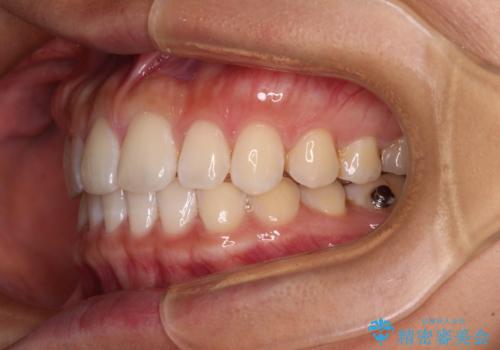

【モニター】前歯のすきっ歯をインビザラインで改善

- 上顎前歯の隙間と口元の突出感を気にして来院された患者様です。

高校生の時に行った矯正治療の後戻りであり、歯列不正は軽度であったので、インビザラインにて治療を行うこととしました。

すきっ歯はあっという間に後戻りを起こすので、可及的に後戻りを防止するために、上下前歯部を舌側からワイヤーで固定しています。

通常は下顎前歯のみに行っていますが、空隙歯列弓では上顎でも行っています。